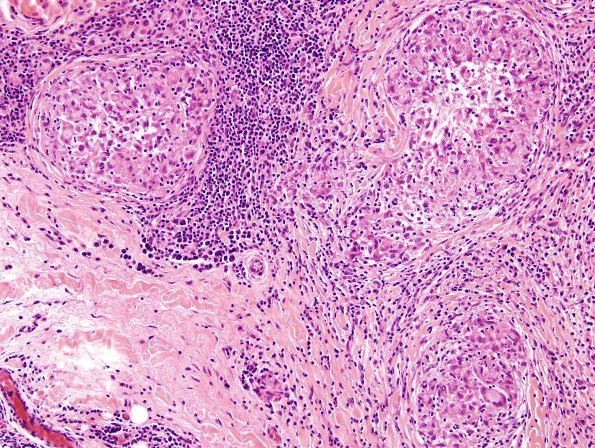

Washington University Experience | PERIPHERAL NEUROPATHY | 10 INFECTION | 4 Leprosy – Tuberculoid | 3A6 Leprosy, tuberculoid (Case 3) H&E 7

3A6-10 The axons were essentially absent in the presence of well formed granulomas composed of lymphocytes and epithelioid histiocytes with relatively few multinucleated giant cells. (H&E)